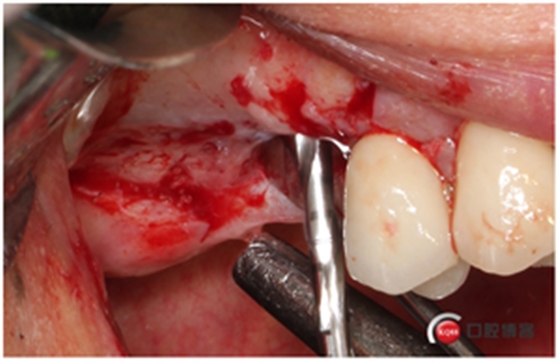

這個東西叫窗口修整鉆,頭兒是圓的且很光滑,四周是有切割功能的,用圓頭頂開上頜竇膜800-1200轉(zhuǎn)速修整窗口邊緣。

我有好的工具我任性,看看我在遠(yuǎn)中用幾秒鐘的時間再開一個窗口。

用大直徑的修整鉆修理邊緣,形成一個規(guī)則的橢圓形窗口。

當(dāng)然了,雖然開始有水壓剝離,但不見得我們需要的位置都能撥開,還需進(jìn)一步剝離一下。然后牙槽嵴頂備洞。